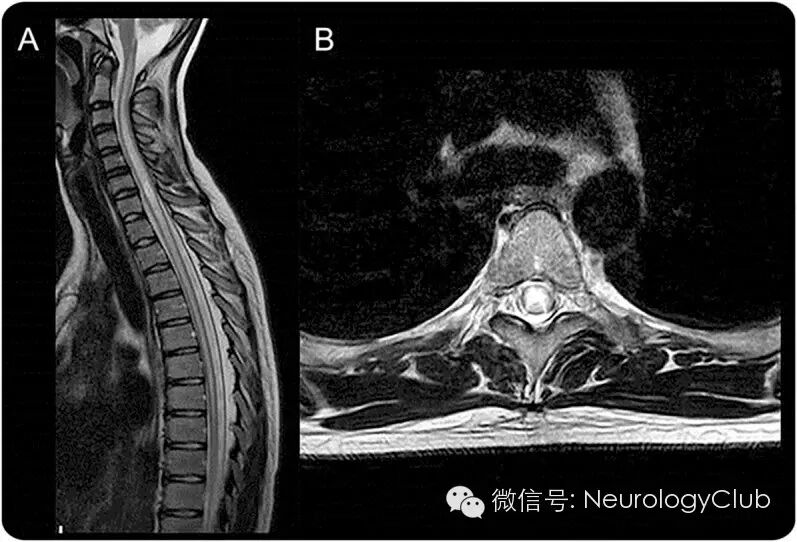

NMO最特征性的表现为长节段横贯性脊髓炎(LETM),即脊髓病变长度大于3个连续的脊髓节段,脊髓MRI上可见病灶主要累及中心灰质区域(图4)。但是,并不是所有的LETM都是NMOSD,目前有几组针对LETM患者的研究显示,AQP4抗体阳性组和阴性组在人口学和临床特点上均有明显差异。LETM对于诊断NMO的特异性在儿童患者中要低于成人。LETM常见于罹患急性播散性脑脊髓炎的患儿,也可在17%的MS患者中出现,还可在67-88%的单相病程的横贯型脊髓炎患儿中观察到。因此,当患者表现为LETM时,需要考虑除了NMOSD以外的其他疾病的可能。

NMOSD随访过程中的脊髓病变:NMOSD病程中LETM的MRI改变已被观察到,MRI资料显示,LETM在疾病恢复期或者应用大剂量糖皮质激素治疗后,可能发展为多个短的病灶。此外,复发性脊髓炎可导致脊髓萎缩,可能引起神经功能障碍。因此,定期行MRI检查对于诊断LETM有着重要意义。

(A:累及胸髓的长节段病变;B:灰质选择性受累[H形脊髓病变])